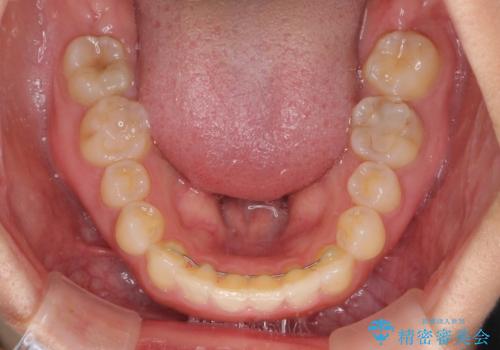

- 前歯の空隙と矮小歯を気にして来院された患者様です。

上下の歯列不正はインビザラインにより整えることとしました。

矯正治療の後に、前歯1歯と奥歯をオールセラミックにて治療することとしました。

矯正治療により矮小歯前後にスペースを作りながら歯列を整え、セラミッククラウン装着後に最終的に歯列と咬合を仕上げました。